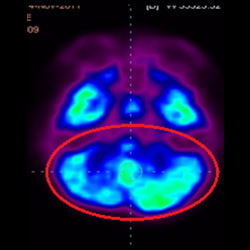

細胞治療前 PET CT 掃描顯示神經(jīng)組織中的藍/黑色區域,表明腦癱引起的大腦損傷。

細胞治療后,藍色和黑色區域減少,并且看到更活躍的區域。這表明損傷減少并改善了大腦功能。